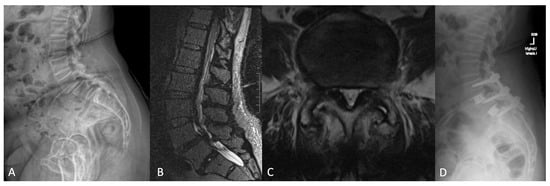

Representative Case

- Tabarestani, T.Q.; Salven, D.S.; Sykes, D.A.W.; Bardeesi, A.M.; Bartlett, A.M.; Wang, T.Y.; Paturu, M.R.; Dibble, C.F.; Shaffrey, C.I.; Ray, W.Z.; et al. Using Novel Segmentation Technology to Define Safe Corridors for Minimally Invasive Posterior Lumbar Interbody Fusion. Oper. Neurosurg. 2023. [Google Scholar] [CrossRef] [PubMed]